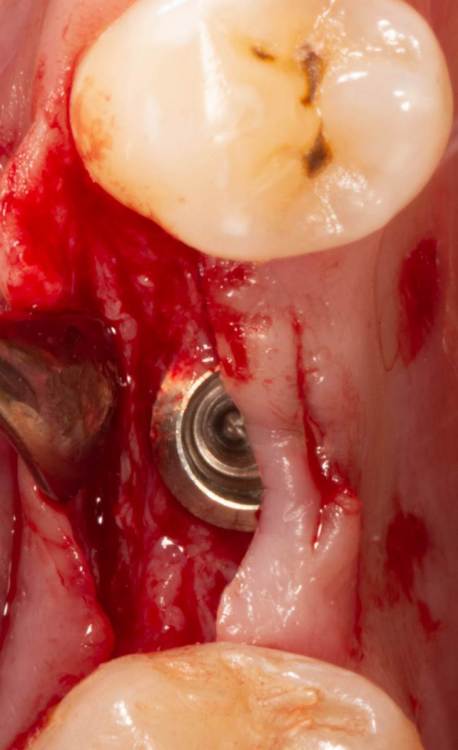

Женька Опубликовано 3 июля, 2023 Автор Поделиться Опубликовано 3 июля, 2023 А здесь вроде результат получше, как считаете? 1 Ссылка на комментарий

TIGER Опубликовано 5 июля, 2023 Поделиться Опубликовано 5 июля, 2023 @Женька что не нравится?не вижу криминала тут Ссылка на комментарий

Женька Опубликовано 5 июля, 2023 Автор Поделиться Опубликовано 5 июля, 2023 @TIGER криминал в соседней теме) Ссылка на комментарий